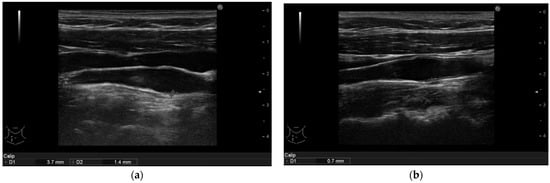

3.4. Ultrasonographic Findings

| Arterial Intima Media Thickness | Baseline Median (IQR)  | 6-Month Follow-Up Median (IQR) | p-Value |

| Intima media thickness of the right carotid arteries (mm) | 1.1 (1.0–1.3) | 0.8 (0.6–0.9) | <0.001 |

| Intima media thickness of the left carotid arteries (mm) | 1.1 (0.9–1.35) | 0.7 (0.6–0.9) | <0.001 |

| Intima media thickness of the right brachial arteries (mm) | 0.75 (0.6–0.9) | 0.6 (0.5–0.7) | <0.001 |

| Intima media thickness of the left brachial arteries (mm) | 0.8 (0.6–0.9) | 0.5 (0.5–0.7) | <0.001 |

| Intima media thickness of the right femoral arteries (mm) | 0.9 (0.8–1.05) | 0.7 (0.5–0.9) | <0.001 |

| Intima media thickness of the left femoral arteries (mm) | 0.8 (0.6–1.1) | 0.7 (0.5–0.8) | <0.001 |

| Cumulative area of the non-calcified plaques in all arteries (mm2) | 3.0 (1.8–6.4) | 1.6 (1.1–7.5) | 0.062 |